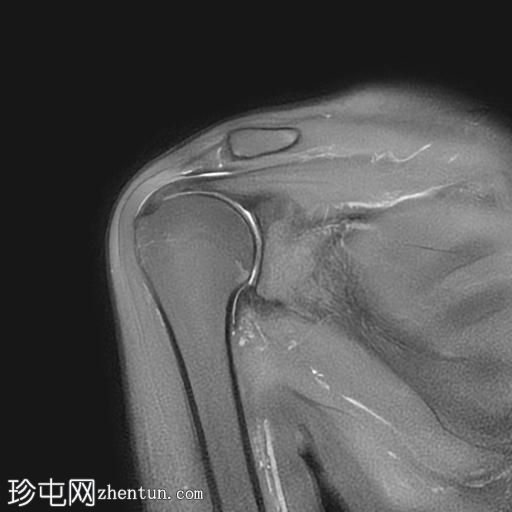

MRI

冠状位

T2加权像

T1加权像

冠状位PD加权像

脂肪抑制像

矢状位

PD加权像

轴位PD加权像

冈下肌腱上部纤维可见约4×6 mm的低信号强度肌腱内病变,提示钙化性肌腱炎

肩峰类型:II型

肩峰下滑囊-三角肌下滑囊可见轻度液体信号

病例讨论

MRI结果提示冈下肌腱钙化性肌腱炎,导致年轻女性患者肩痛及活动受限。肩袖钙化性肌腱炎是一种自限性疾病,由羟基磷灰石钙沉积引起,最常见于冈上肌腱。